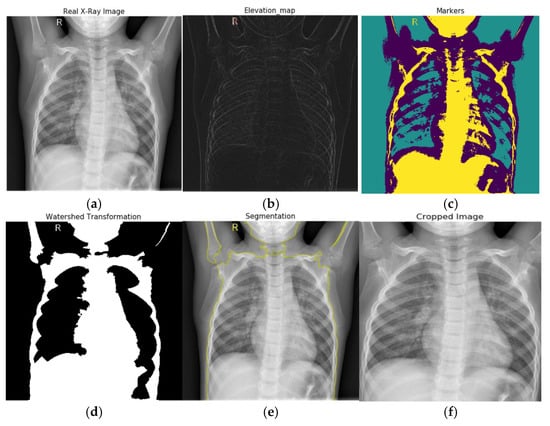

3.2. Watershed Based Region Growing Segmentation